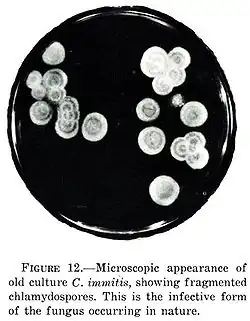

C. immitis can cause a disease called coccidioidomycosis (valley fever).[8][9][10] Its incubation period varies from 7 to 21 days.[11] Coccidioidomycosis is not easily diagnosed on the basis of vital signs and symptoms, which are usually vague and nonspecific. Even a chest X-ray or CT scan cannot reliably distinguish it from other lung diseases, including lung cancer. Blood or urine tests are administered, which aim to discover Coccidioides antigens. However, because the Coccidioides creates a mass that can mimic a lung tumor, the correct diagnosis may require a tissue sample (biopsy). A Gomori methenamine silver stain can then confirm the presence of the Coccidioides organism's characteristic spherules within the tissue. The C. immitis fungus can be cultured from a patient sample, but the culture can take weeks to grow and requires special precautions on a part of the laboratory staff while handling it (screw cap vials and sterile transfer hoods are recommended).[12] It is reported as the tenth-most often acquired infection in the laboratory conditions with two documented deaths.[2] Until October 2012, C. immitis had been listed as a select agent by both the U.S. Department of Health and Human Services and the U.S. Department of Agriculture, and was considered a biosafety level 3 pathogen.